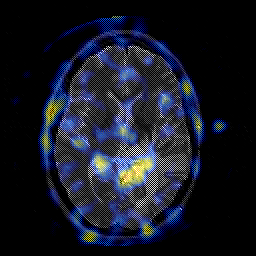

Glioblastoma multiforme overlay -- Slice #28

[Home][Help][Clinical][Tour 1][Tour 2][Tour 3] Slice 28